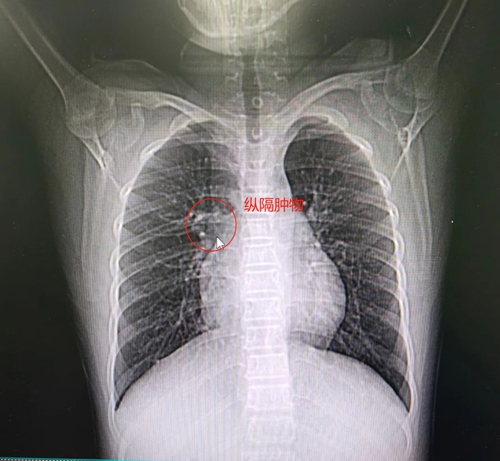

小明(化名)今年9歲,因經(jīng)??人缘结t(yī)院做ct檢查,結(jié)果顯示有縱隔占位、大小約2cm*2cm。

醫(yī)院心血管麻醉團隊共同研究了病情,進行了全面細致地評估,完善術(shù)前各項檢查,制定嚴密的麻醉及手術(shù)方案,對患者采用當下國際領先的麻醉技術(shù)——非氣管插管自主呼吸麻醉下行胸腔鏡縱膈腫物切除術(shù)。

術(shù)中手術(shù)團隊成員緊密配合,手術(shù)過程流暢、操作嫻熟,手術(shù)切口僅僅1cm,術(shù)中出血僅有2mL,歷經(jīng)0.5小時為小明切除了縱膈腫物,全程保留自主呼吸,術(shù)前無尿管,術(shù)中無插管。